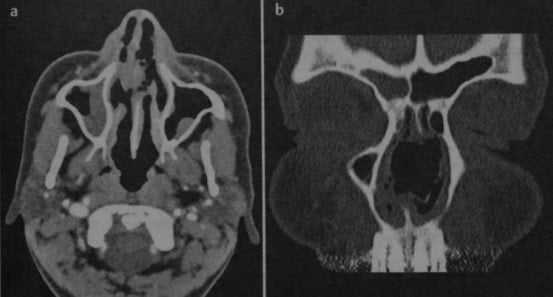

Гранулематоз Вегенера. КТ: объемное образование в полости носа (а), разрушающее носовую перегородку (b). Образование расположено по средней линии, имеет плотность мягких тканей. Первичная находка у пациента с жалобами на головные боли.

- Очаг поражения округлой формы, имеющий плотность мягких тканей

- Часто расположен по средней линии

- Затемнение полости носа и придаточных пазух носа

- В некоторых случаях наблюдается деструкция кости по типу «изъеденности молью»; первоначально поражается перегородка носа, позднее - медиальная стенка верхнечелюстной пазухи и носовые раковины.